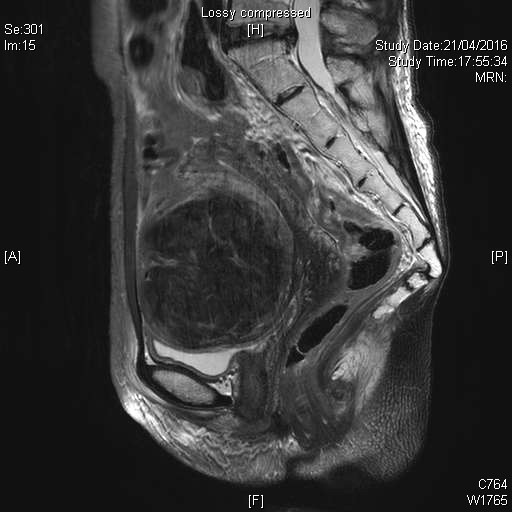

長有大子宮肌瘤的女性患者